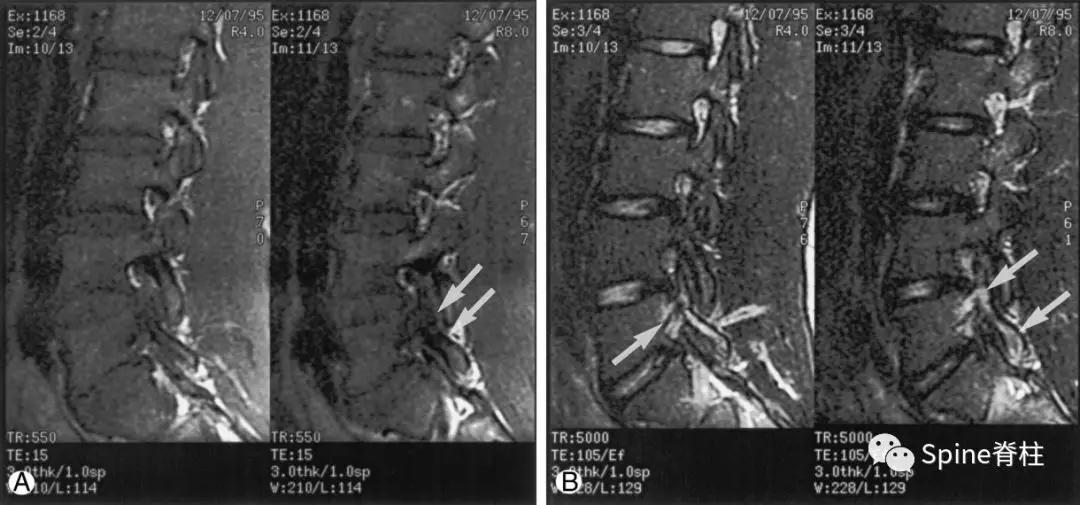

图:孤立的峡部水肿信号,提示L5右侧峡部裂(1级)

16岁的足球运动员诉右腰部疼痛。A:右侧T1加权像可见腰5峡部和椎弓根呈低信号(箭头);B:右侧T2加权像可见腰5峡部、椎弓根和关节突呈高信号(箭头)。

图:T2水肿信号且峡部皮质不连续断裂

提示L3左侧峡部裂(2级)

17岁的篮球运动员诉腰痛。A:T1像,左侧腰3峡部呈不连续的低信号(箭头);B:T2像,左侧腰3椎弓根和峡部呈高信号(箭头)

图:峡部完全断裂,断端存在明显间隙,且T2像明显水肿信号,提示L5左侧峡部裂(3级)

16岁的足球运动员,诉腰痛,以左侧为重。A:T1像可见腰5左侧峡部完全断裂(箭头);B:T2像,腰5左侧峡部、椎弓根和关节突水肿信号(箭头)

图:峡部完全断裂,但无T2水肿信号

提示为左侧L5峡部裂(4级)

13岁运动员,左侧腰骶部疼痛。A:T1像,左侧腰5峡部完全断裂(箭头);B:T2像,左侧腰5峡部清晰可见,骨质无信号改变,峡部缺损处可见轻微的高信号,提示可能为肉芽组织或积液